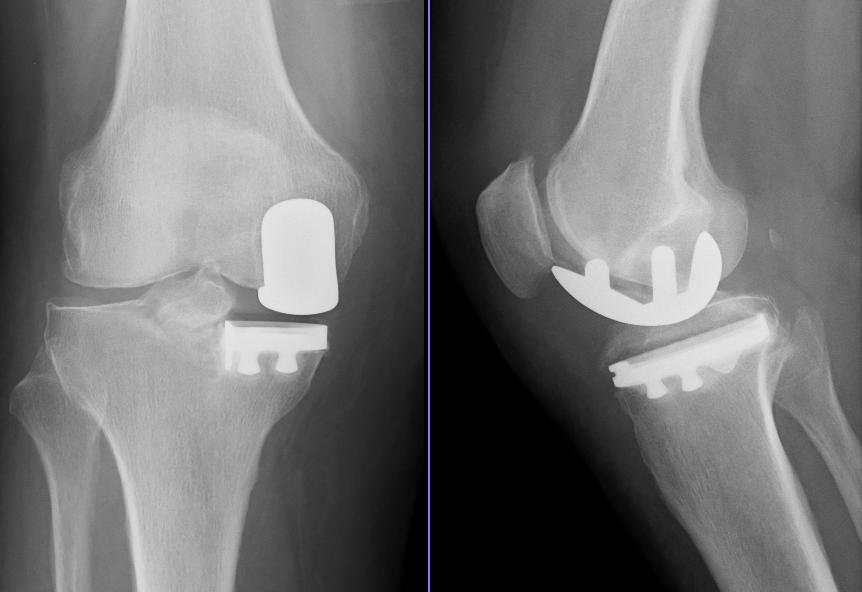

Knee replacement surgery, also known asknee arthroplasty, is regarded as a modern surgical procedure that can accurately be described as “knee resurfacing”. This procedure entails restoring the weight bearing facade of the knee joint that is damaged, worn out, or diseased to relieve pain and movement disability. It is performed through the implant of an orthopedic metal and plastic component shaped as a joint so that the knee can move properly.

1) TKR (Total knee replacement): The surgery involves the replacement of both sides of the knee joint. It is the most common procedure. Surgery lasts between one and three hours. Experts say that the implant will last from 15 to 20 years. Despite having much less pain and better mobility, there will be scar tissue, which means there will always be some difficulty in moving and bending the knees. Most surgeons believe that TKR is a more reliable long term procedure.

2) PKR (Partial knee replacement) :This surgery is done when only one side of the knee joint is replaced. Hence, it does not last as long as a total replacement. Less bone is removed, so the incision is smaller.PKR is suitable foraround one in four people with osteoarthritis. Post-operative rehabilitation is simpler, there is less blood loss, lower risk of infection and blood clots. PKR in general includes a shorter hospital stay and recovery period.PKR often results in more natural movement in the knee. Most PKR patients are able to get up and about after their their operation more rapidly than TKR ones.